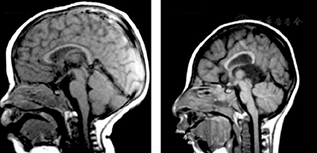

胎儿小头畸形症在孕妇妊娠24周左右即可应用超声、磁共振等技术发现患儿头围测值及脑容量低于正常同龄胎,临床上常用正常同龄儿头围3个标准差作为诊断小头畸形症的依据。一名在巴西工作的斯洛文尼亚妇女,妊振13周时受寨卡病毒感染,在妊娠14~20周时超声检查正常;返回欧洲后,在妊娠29周时作超声检查,提示胎儿出现畸形表现,胎动减少;妊娠32周时胎儿生长受限,胎盘厚度3.5 cm(正常范围),脑室中度扩大,小脑径低于标准,脑结构模糊,有多个钙化灶,胎儿其他结构无异常(图5[23])。应患者要求于妊娠32周终止妊娠,分娩出小头畸形婴儿。尸检脑组织样本RT-PCR检测寨卡病毒阳性,切片电镜检查发现黄病毒样微粒染色阳性,证实寨卡病毒可垂直传播致胎儿严重脑组织病变,除脑组织外胎儿其他器官无明显病变,提示寨卡病毒具有极强的嗜神经性[23]。

注:A.B超检查可见胎儿脑内多处钙化(箭头所示)及侧脑室枕角扩张(虚线标所示);B. B超检查可见多处胎盘钙化;C.胎儿脑皮质和皮质下白质多处钙化(长箭头所示),皮质完全无脑回,基底节已发育但不清晰(黑色星号所示),两侧大脑侧裂全开放(短箭头所示),第三脑室未扩张(白色星号所示);D.侧脑室体部扩张(白色箭头所示),左侧已塌陷,侧脑室颞角亦扩张(短箭头所示),丘脑(黑色星号所示)和左侧海马(白色星号所示)发育良好,对侧因尸检原因未观察到